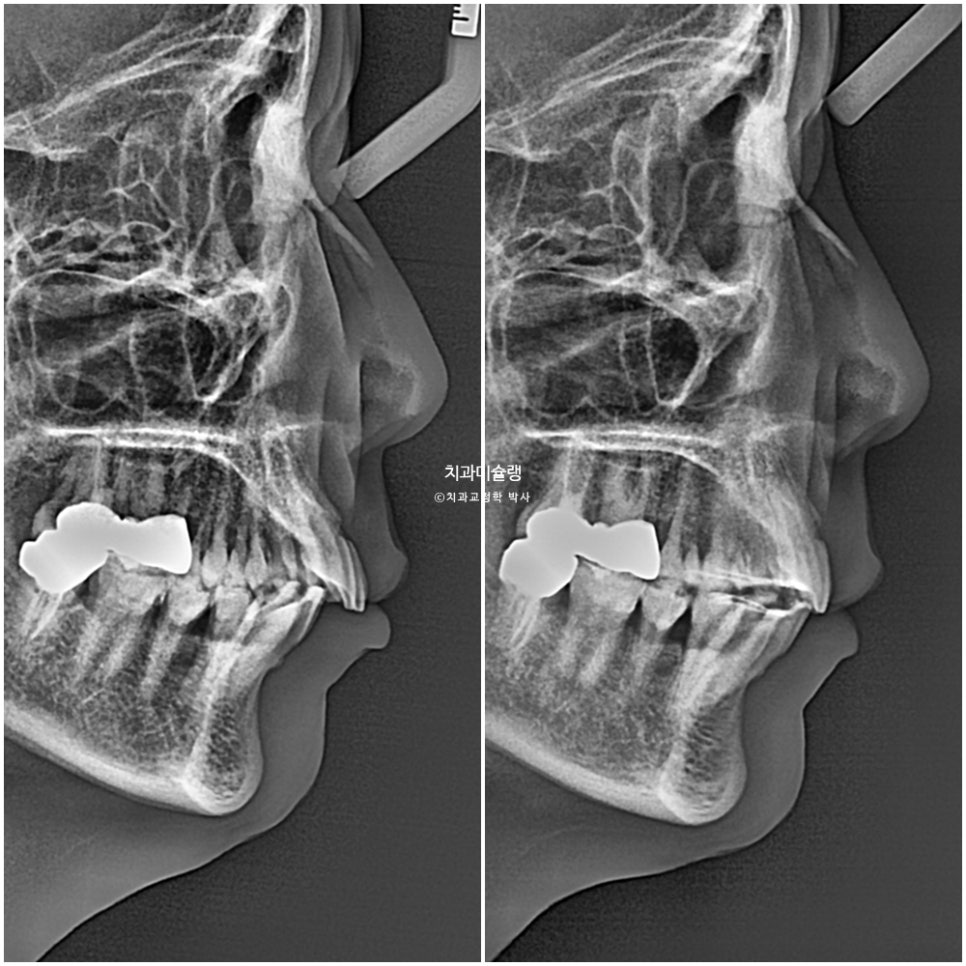

앞니 돌출이 심해서 입이 편하게 다물리지 않습니다.

턱끝까지 힘을 주어야 다물리는 상태를 입술부전증 이라고 합니다.

턱끝에 힘이 들어가니 턱끝 모양이 늘 울퉁불퉁한 호두턱 자갈턱 상태입니다.

물론 어금니 교합관계가 좌우가 약간 다르기 때문에 중심선이 정확히 매치되지 않는 한계점이나, 심하게 뻗친 앞니 각도가 완전히 정상치만큼 줄어들진 않겠지만

앞니 뻗침도 소량 개선되었습니다.

앞니 돌출 해소로 입술부전증이 해소되어 턱끝에 힘이 풀리며 호두턱(자갈턱)이 없어졌습니다.

돌출된 위 앞니가 뒤로 들어가며 아랫입술이 편하게 물립니다.

교정기간동안 치근흡수는 없으며, 치근평행도는 양호합니다.